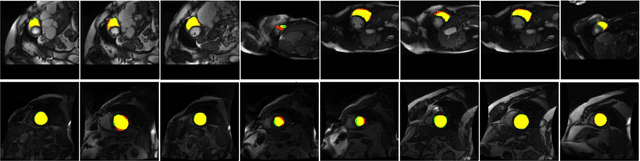

Abstract:Normalization layers are essential in a Deep Convolutional Neural Network (DCNN). Various normalization methods have been proposed. The statistics used to normalize the feature maps can be computed at batch, channel, or instance level. However, in most of existing methods, the normalization for each layer is fixed. Batch-Instance Normalization (BIN) is one of the first proposed methods that combines two different normalization methods and achieve diverse normalization for different layers. However, two potential issues exist in BIN: first, the Clip function is not differentiable at input values of 0 and 1; second, the combined feature map is not with a normalized distribution which is harmful for signal propagation in DCNN. In this paper, an Instance-Layer Normalization (ILN) layer is proposed by using the Sigmoid function for the feature map combination, and cascading group normalization. The performance of ILN is validated on image segmentation of the Right Ventricle (RV) and Left Ventricle (LV) using U-Net as the network architecture. The results show that the proposed ILN outperforms previous traditional and popular normalization methods with noticeable accuracy improvements for most validations, supporting the effectiveness of the proposed ILN.